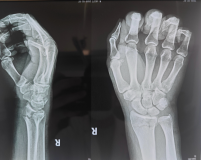

接诊的主治医师杜龙龙第一时间完成体格及X线影像检查,结果显示,右桡骨远端骨折,且骨折线已穿透关节面。关节面骨折如同精密齿轮错位,复位时哪怕1毫米的偏差,都可能留下腕关节僵硬、创伤性关节炎的后遗症。面对复杂病情,杜龙龙医师迅速联系科主任董博及副主任医师周健进行会诊。

在充分告知并获得患者及家属知情同意后,杜龙龙主治医师在董博主任和周健副主任医师现场指导下,为何先生实施手法复位。凭借扎实的解剖知识与丰富的临床经验,团队精准把控复位力度与方向,通过轻柔而稳健的操作,逐步纠正骨折端的移位与畸形。整个过程流畅高效、一气呵成。复位完成后,复查X线片显示,骨折对位对线良好,关节面恢复平整,达到理想复位标准。何先生当即感到腕部疼痛显著缓解,扭曲的手腕形态恢复正常,对治疗效果连连称赞。